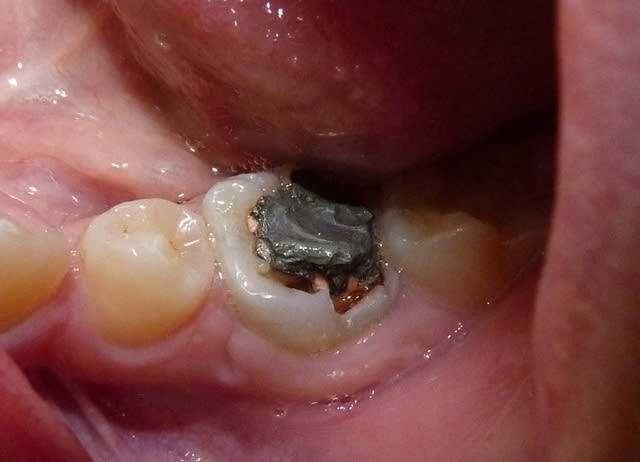

Vu cet après-midi : 26 délabrée par MIH et manque hygiène incluse sous 65. La maman consulte car ne veut pas enlever la dent, OK pour le HN.

Je vais avulser 65, cureter, mettre un MTA et un CVI, attendre 1 mois pour avoir un peu d'egression et faire ma CPP. Il faudra ensuite probablement un passage chez l'ortho pour redresser l'axe.